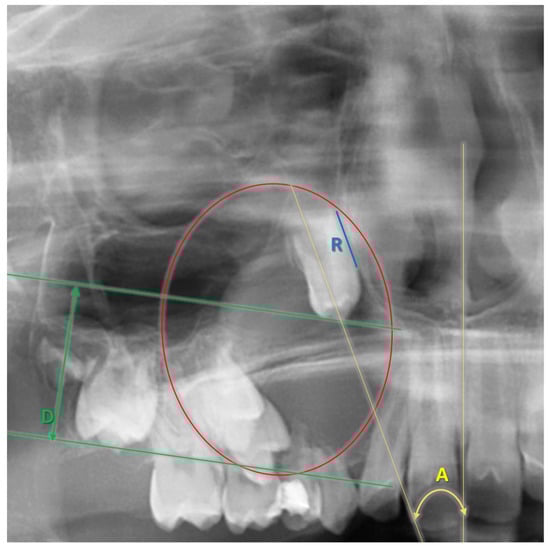

In the presented case, the prompt eruption of Tooth 13 after marsupialization was possible due to the existence of promising factors, as described above and highlighted in Figure 15. The apex was open, and the root (R) did not achieve 2/3 of its final length. Because the adjacent teeth were malpositioned, as a reference line to assess angulation (A), the midline was chosen (as an analogy to Ericson and Kurol’s classification) [38]. The low value of the angle and almost-parallel position of the canine germ according to the midline gave a reasonable assumption that a spontaneous eruption was possible. The cusp depth (D) is appropriate to the stage of development because, according to Coulter et al. [39], the predominant vertical eruption path can be still expected. The upper right premolars revealed a less favorable position, inclined more horizontally. CBCT confirmed vesibuloposition with a poor alveolar boundary condition that required careful application of orthodontic force to achieve their proper alignment.

Figure 15.

Factors determining the chance for spontaneous eruption after marsupialization A—angulation; D—depth of cusp; R—root development.